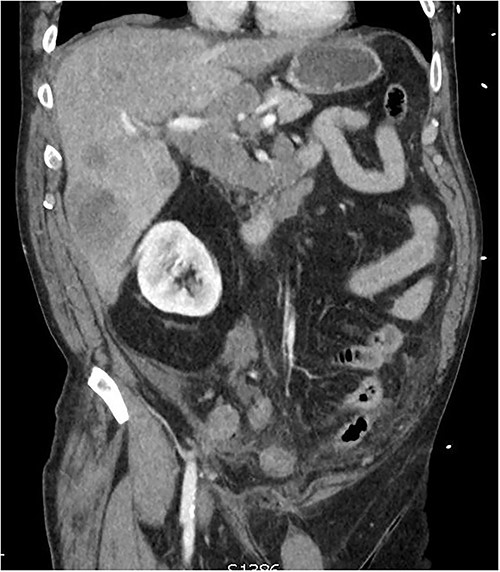

CT of the abdomen from admission demonstrating hepatic lesions, lymphadenopathy and a perforated appendix.

A 60-year-old male presented with 4-h history of acute right lower abdominal pain. He had a history of emphysema, hypertension, heavy cigarette smoking and prostate cancer in remission. On presentation, he was septic with tachycardia (110/min), hypotensive with systolic blood pressure of 90 mmhg and febrile (38.5°C). Abdominal examination revealed peritonism in the right lower quadrant. Computed tomography (CT) scan was performed demonstrating a perforated appendix with a 51 × 31 × 26 mm collection and surrounding fat stranding. CT scan also demonstrated innumerable hepatic nodules, mural thickening of the caecum and sigmoid colon as well as marked mesenteric, para-aortic, portocaval lymphadenopathy and pulmonary consolidation/collapse in the right lower lobe (Fig. 1). Patient underwent an exploratory laparotomy. Intra-operative findings were of a perforated appendix with four quadrant purulent contamination and a thickened and woody sigmoid colon. A subtotal colectomy with end ileostomy was performed. Post operatively the patient remained intubated and ventilated.